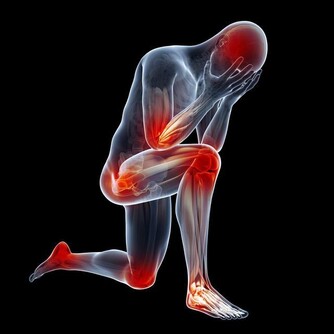

3、或是心功能減退。手腳冰冷和心臟功能有很大的關係,因為血液是由心臟發出,攜帶氧氣到全身各部位,糖經過氧化後,才能產生熱能,手腳才會溫暖。一旦心功能減退,就會影響血液運行輸送,造成手腳冰冷的情形。比如心臟衰弱會導致身體末梢部位血液供應大幅減少,使末梢溫度降低。

1、多做運動。讓身體動起來,有利於加快新陳代謝和血液循環,簡單動作如爬樓梯、原地蹦跳等都有助加快體內熱量的釋放。